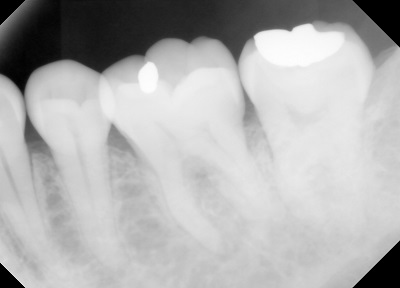

口腔がんの診断

口腔がんは他の消化器がんと同じようにびらんや潰瘍を伴います。その周辺は堤防状の盛り上がり硬結を伴うことが多いです

粘膜上皮の白板、紅板などの色調の変化にも注意が必要です

最終的には病理組織検査で確定診断になりますが、目で見ることが可能なため粘膜疾患の発見は安易です。